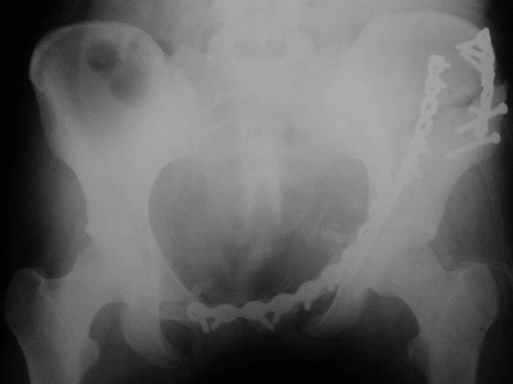

Рентгенограммы после операции

Прямая проекция

inlet

подвздошная

запирательная